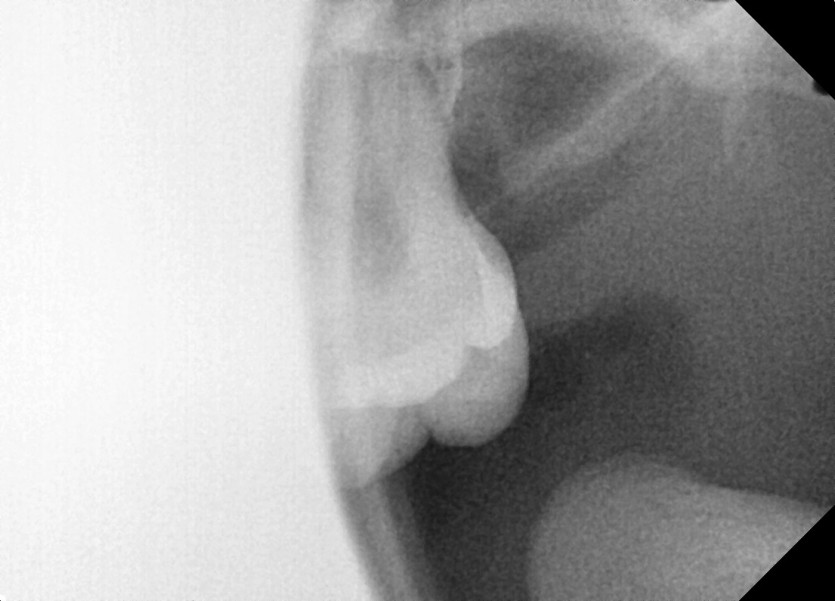

#28 사랑니 발치

구강 외과 전문의가 당일 발치했습니다.